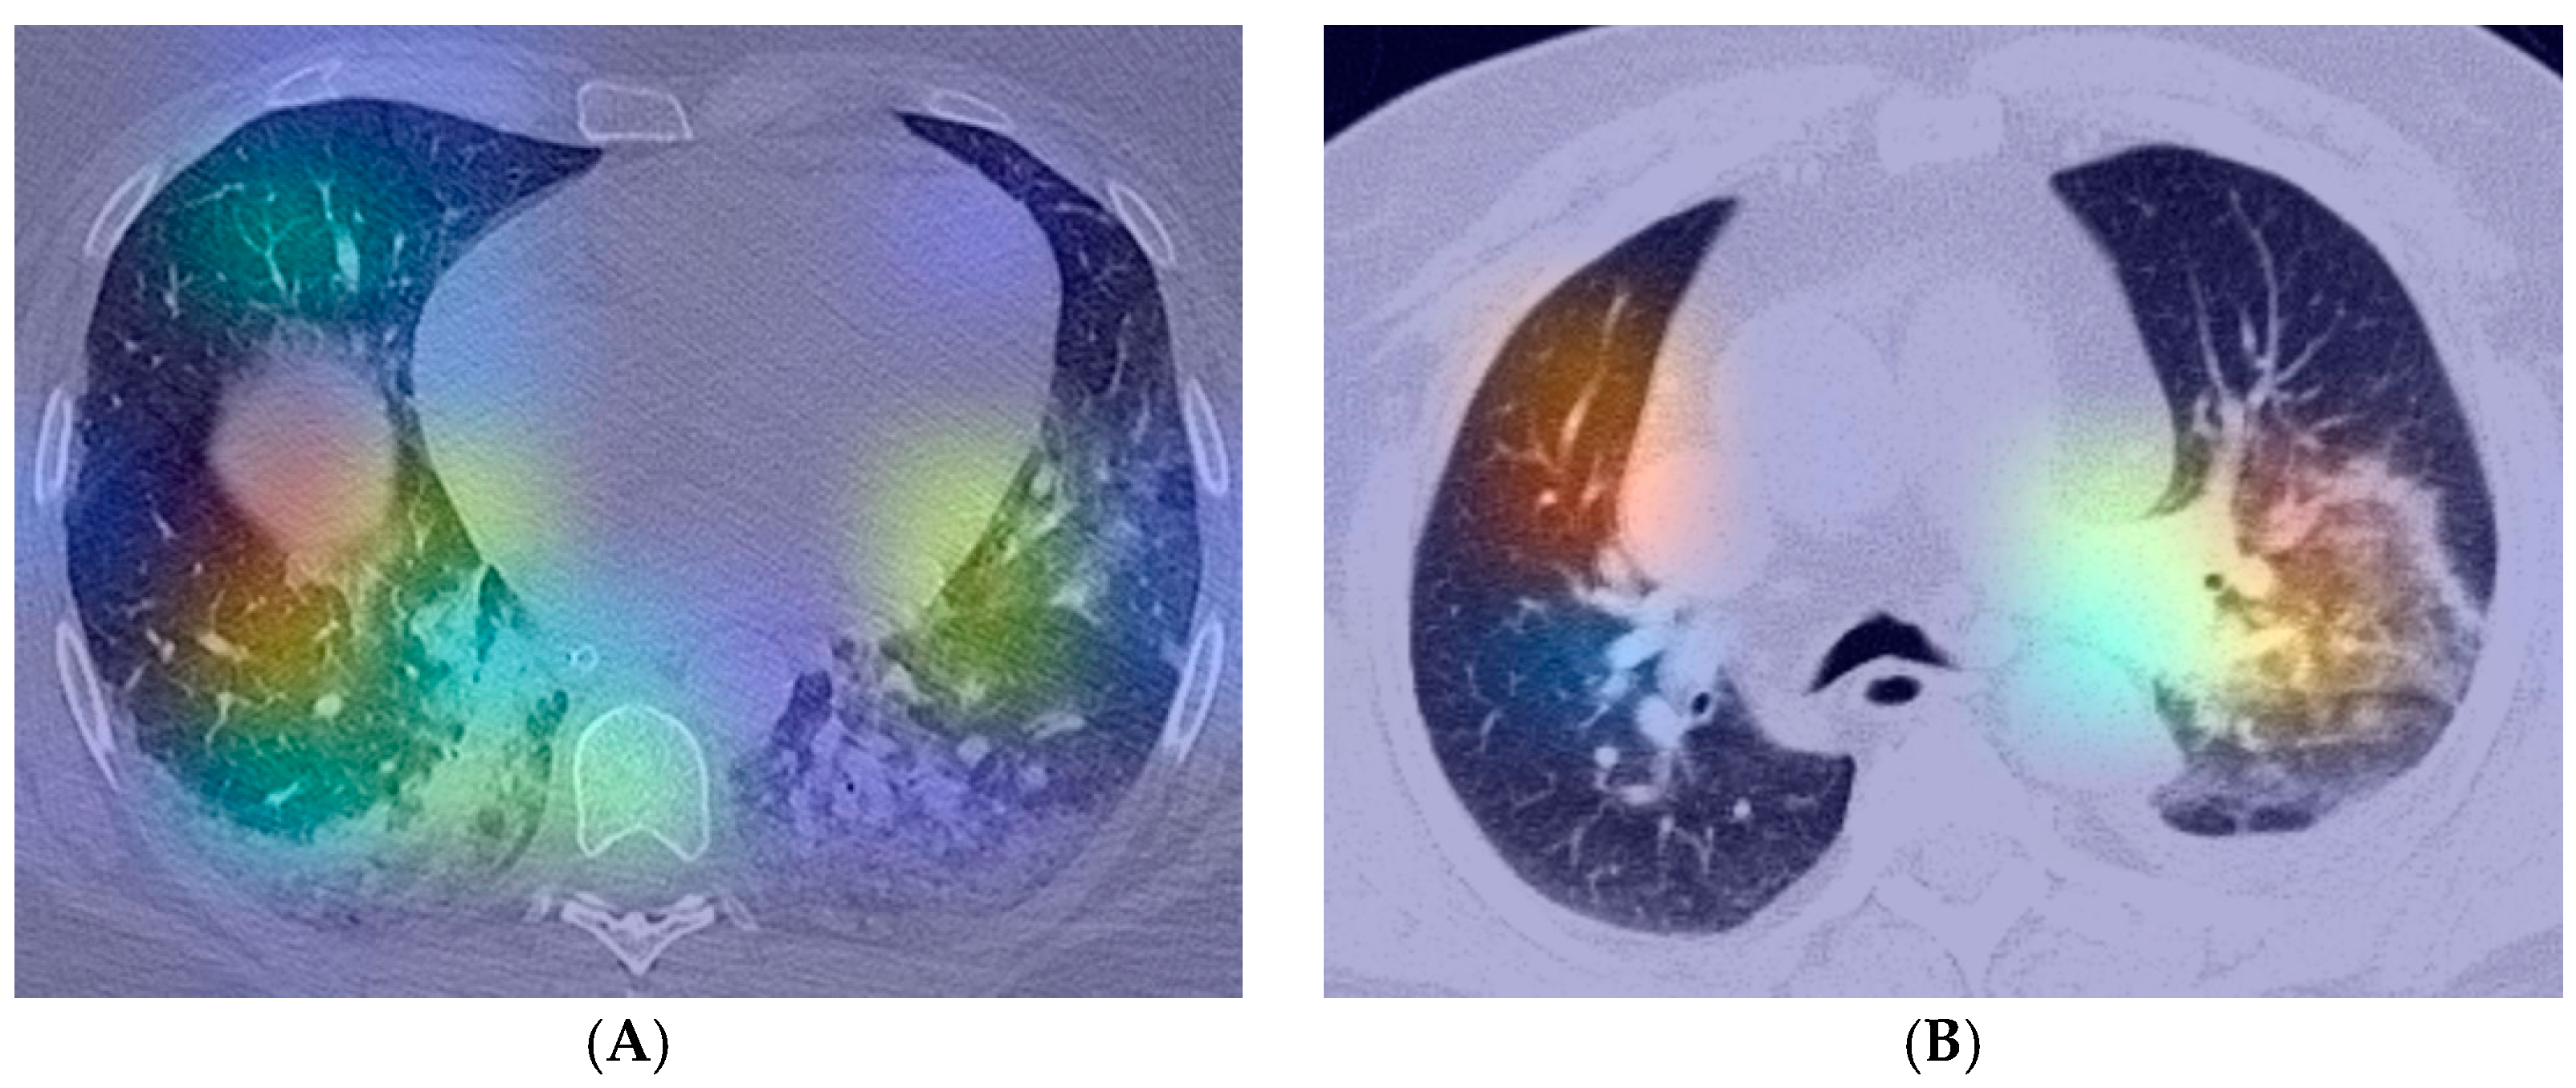

- Selvaraju, R.R.; Cogswell, M.; Das, A.; Vedantam, R.; Parikh, D.; Batra, D. Grad-CAM: Visual Explanations from Deep Networks via Gradient-based Localization. Int. J. Comput. Vis. 2020, 128, 336–359. [Google Scholar] [CrossRef] [Green Version]